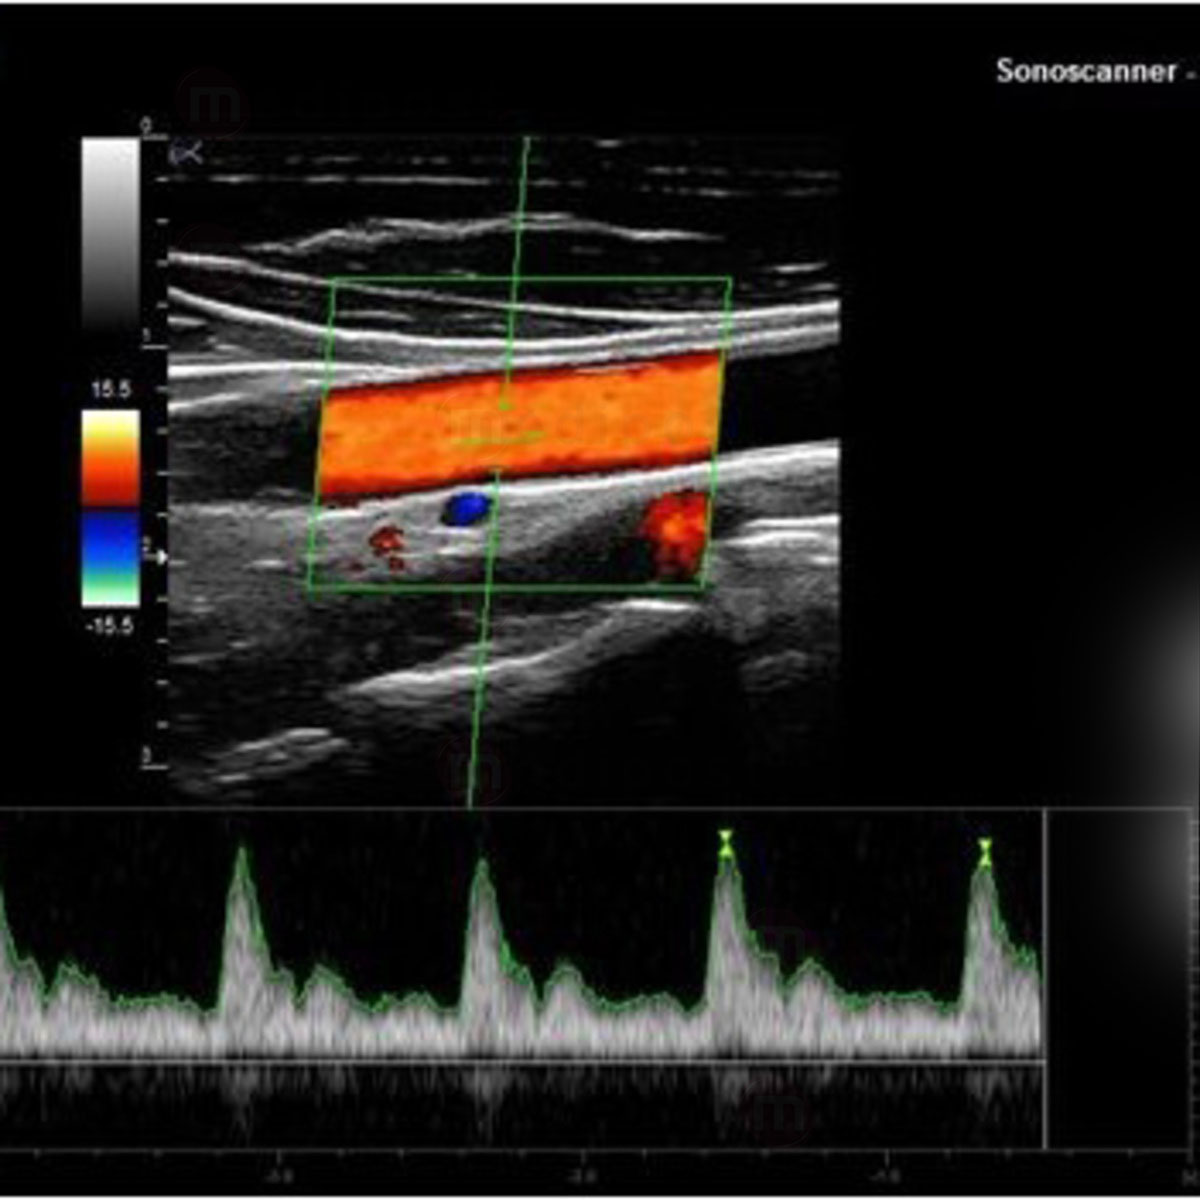

- Doppler Pulsé (PW)

- Doppler Couleur

- Mode Duplex

- Mode Triplex

- Vasculaire

- Sonde Linéaire HD Très haute fréquence 8-18 MHz (Parties molles, Vasculaire, Anesthésie, MSK, Médecine du sport, Pédiatrie)

- Sonde linéaire 5-10 MHz (Parties molles, Vasculaire, Anesthésie)